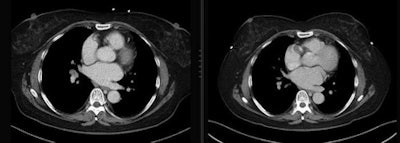

For their study, the authors aimed to evaluate the proportions of the female breast and glandular tissue that are within the range of angle-dependent tube current modulation, and whether the proportions could be optimized by keeping the bra on. They also looked into whether the metal parts of bras cause artifacts that impair the diagnostic value of the images.

The results showed that 91.3% of total breast tissue and 96% of glandular tissue were within the region of tube current reduction in group A. The same values were 60.4% and 67.1%, respectively, for group B.

The impact of wearing a bra varied in patients with different cup sizes. Cup size A saw the best results, with 97.5% of breast tissue and 98.1% of glandular tissue inside the reduction region with a bra, the authors wrote. Cup size E showed the biggest improvement: 83.3% of breast tissue and 90% of glandular tissue were covered using a bra, compared with only 30% of breast tissue and 31.8% of glandular tissue without the undergarment.